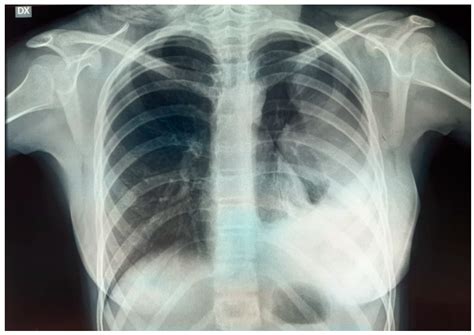

• Extent of Disease at Diagnosis: This is arguably the most significant factor. Patients with localized disease (cancer confined to the primary site) generally have a better prognosis than those with metastatic disease (cancer that has spread to distant sites like the lungs, bones, or bone marrow).

Improving the Ewing sarcoma prognosis relies heavily on a multimodal treatment approach. Because Ewing sarcoma is a systemic disease, local treatments alone are rarely sufficient. Instead, a combination of systemic chemotherapy, surgical intervention, and radiation therapy is typically required to maximize the chances of long-term survival.

• Local Control: This involves surgery to remove the tumor or radiation therapy (or a combination of both) to kill cancer cells in the primary location.